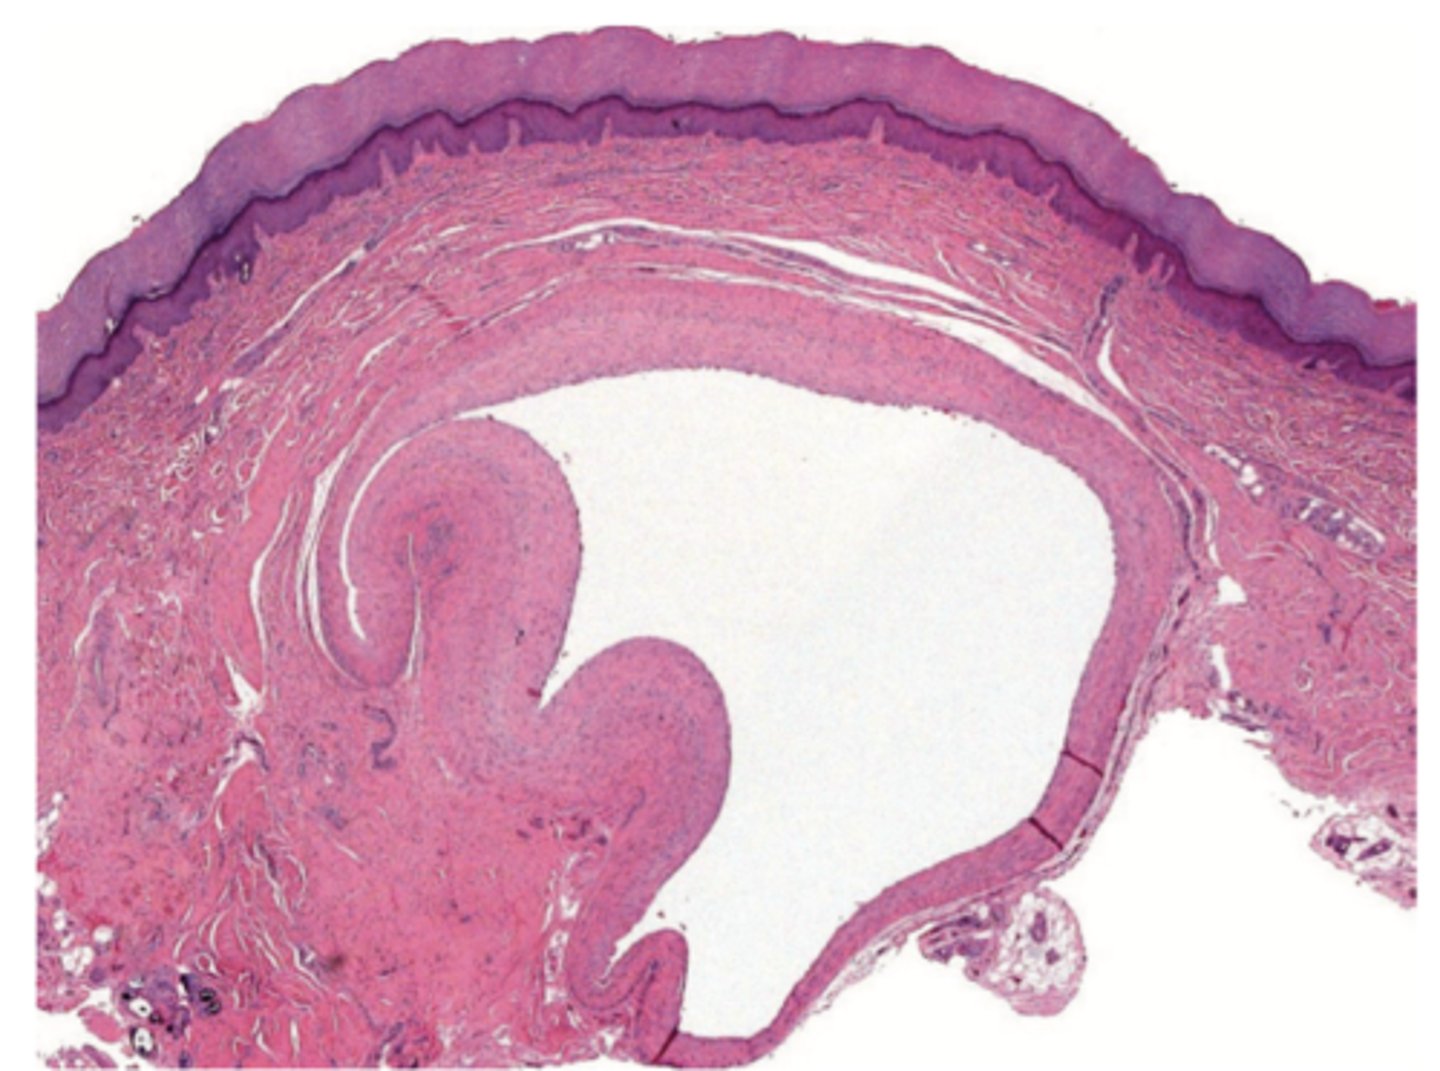

pigmented layer

name 2

rods and cones

ganglion cells

sclera

conjunctiva

cornea